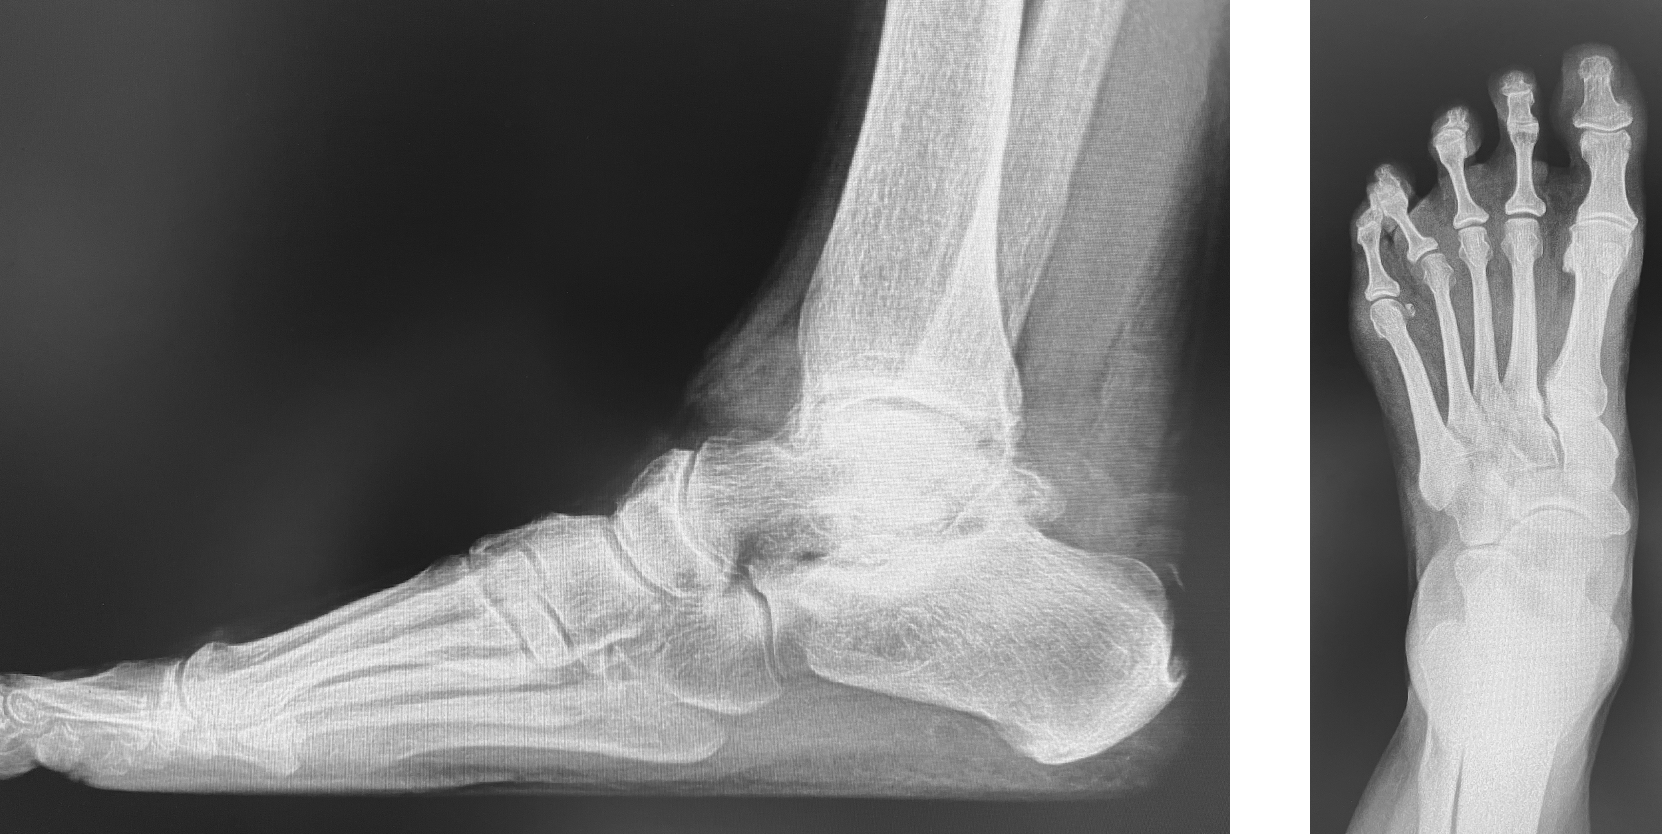

Severe arthrosis was present in the STJ. Surgeons prepped the joint with a combination of osteotomes and curettes. After using a lamina spreader in the posterior facet of the STJ to restore the biomechanical angles, we determined that a 12mm wedge was needed. Prior to inserting the wedge, we determined that a gastrocnemius recession would be sufficient to get the ankle to neutral position and a tendo-Achilles tendon lengthening was not needed. The wedge was designed from a femoral head allograft (from the neck portion) without any frontal plane adjustments. We tamped the graft into the posterior facet and packed the remaining STJ gaps with allogenic bone chips from the remaining allograft. Surgeons inserted two fully threaded screws without lag technique across the STJ (Figure 3) with postoperative lateral Meary’s angle measuring 4°, talar declination angle measuring 22º, and talocalcaneal angle measuring 35º. Suture anchors inserted into the talar neck, fibular tip, and the lateral calcaneus replicated the anterior talofibular and calcaneofibular ligaments. To minimize adhesions, we placed amniotic tissue around each peroneal tendon on the lateral aspect of the sinus tarsi. Lateral incision closure occurred without much tension.